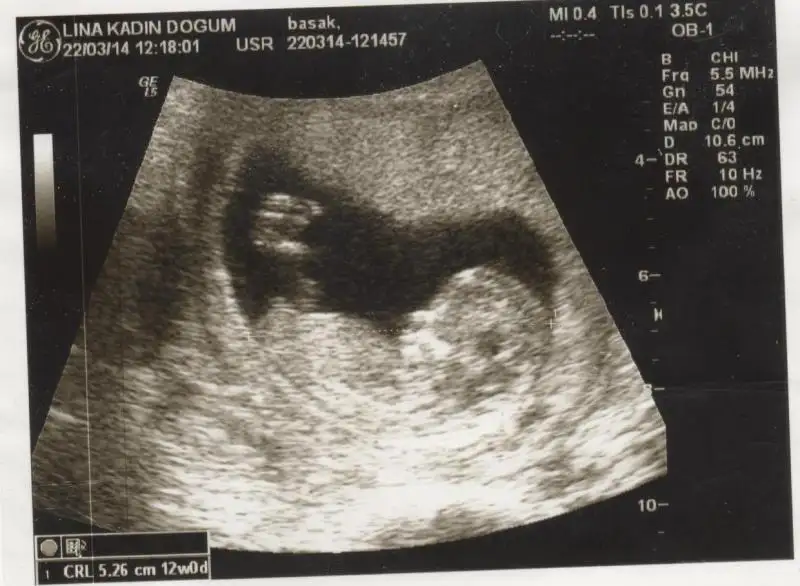

selam kızlar daha once burada usg goruntulerını paylasmıstım :) net sonucu yazayım dedım,erkek..

Eki Görüntüle 1016535

Eki Görüntüle 1016536 Eki Görüntüle 1016536